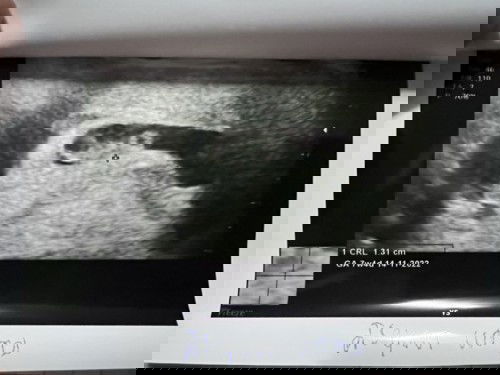

พบถุงตั้งครรภ์ แต่ไม่พบตัวอ่อน

ท้อง2นะคะ ตั้งครรภ์ได้ 8w แล้วค่ะ แต่ยังไม่ได้ฝากครรภ์ เมื่อวานมีอาการเจ็บท้องน้อย และมีเลือดออก ปนมากับปัสสาวะ เลยรีบไปพบหมอ คุณหมอตรวจเลือด ตรวจปัสสาวะ ไม่พบการติดเชื้อ และพบการตั้งครรภ์จริงค่ะ แล้วคุณหมอก็อัลตราซาวด์พบว่ามีถุงตั้งครรภ์แต่ไม่เจอตัวอ่อนค่ะ เป็นการตั้งครรภ์ในมดลูก และคุณหมอก็ทำการตรวจภายในดูปากมดลูก คุณหมอแจ้งว่าปากมดลูกปกติค่ะ และเลือดก็ได้หยุดไหลแล้ว คุณหมอให้กลับมาพักที่บ้าน ให้นอนอยู่เฉยๆ ห้ามเดิน ห้ามยกของ หรือทำอะไรในช่วงนี้ คุณแม่กังวลมากค่ะ ไม่ทราบว่าแม่ๆหลายท่านอัลตราซาวด์เจอตัวอ่อนตอนกี่Wคะ? (ตอนท้องแรกไม่เคยมีอาการอะไรแบบนี้เลยค่ะ) #ขอบคุณล่วงหน้านะคะ #คุณแม่ๆช่วยแนะนำหน่อยค่ะ